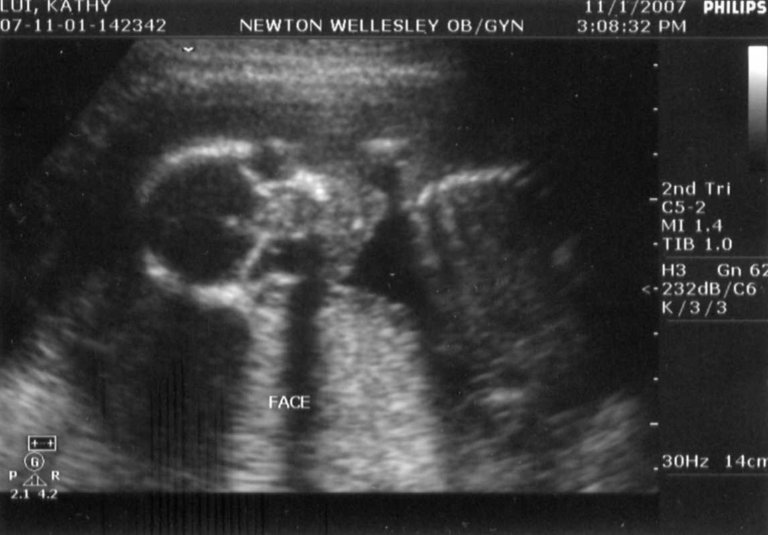

These were back at the doctor's office. Bascially, they did the same set of tests as the Maternal-Fetal

medicine folks did the previous week. This appointment had been scheduled about a month in advance, before

both phases of the integrated screening had been conducted at the hospital. According to my obstetrician,

the results looked good. Again, we got a good guess as to the sex.